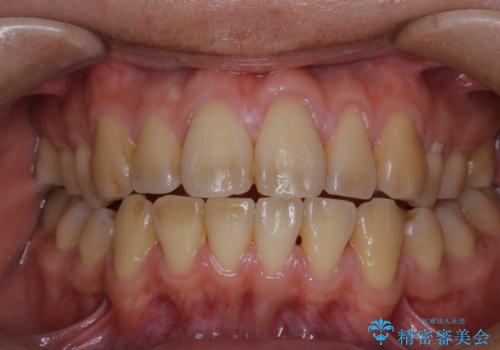

電子タバコによる着色をPMTCできれいに落とす

タバコによるヤニ、着色、歯の汚れをPMTC(60分コース)で除去。